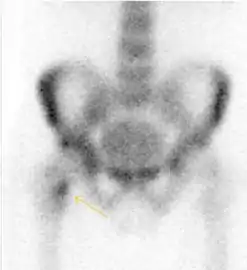

MRI has been shown to have 100% sensitivity and specificity in prospective studies of occult hip fractures. These fractures were diagnosed by bone marrow edema and a low signal fracture line, mainly on T1 or T2 weighted images (Figure 10).[1]

Figure 10:

Stress femoral neck fracture in a young athlete barely visible in X-ray film as a sclerotic line (arrow)[1]

In this case, Tc 99 scintigraphy shows a band of uptake[1]

Furthermore, T1 (left) and DP fat saturated (right) weighted MR images showed the fracture line and a pattern of edema.[1]

Bone scanning in people with hip pain can be complementary to other imaging studies, mainly in indeterminate bone lesions to clarify whether it is an active lesion with abnormal radiotracer accumulation. Nevertheless, MRI has replaced scintigraphy in the diagnosis of most of these conditions. An example is stress or insufficiency fractures: increased uptake is usually present in around 80% of fractures within 24 h, and 95% of fractures reveal activity by 72 h following trauma, showing an overall sensitivity of 93% and specificity of 95%. MRI is superior to bone scans in terms of sensitivity (99%-100%) and specificity (100%). Moreover, a bone scan does not provide detailed anatomical location of the fracture, and further imaging is usually required.[1]